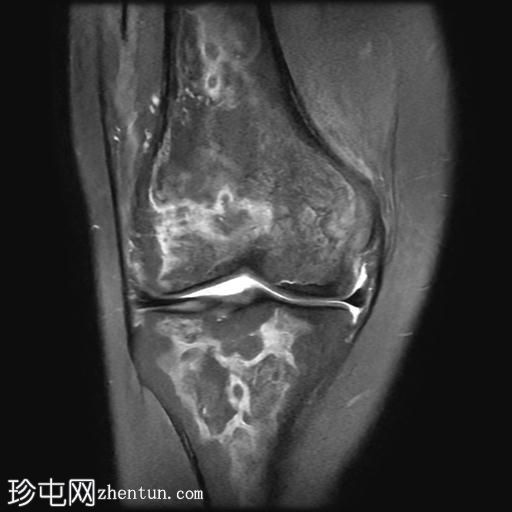

冠状位PD脂肪抑制序列

在股骨远端和胫骨近端的髓腔内可见不规则的蛇形异常信号线。PD图像上,高信号线与骨髓内低信号线的内表面平行。

可见少量关节积液。

股骨远端和胫骨近端可见典型的骨梗死MRI表现。